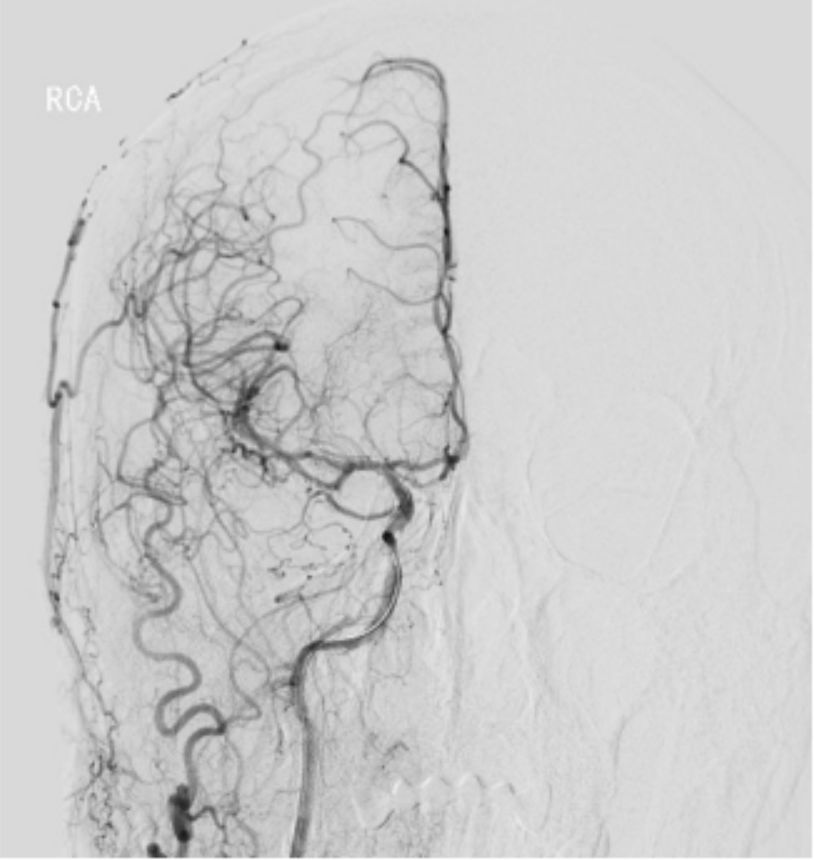

2019-07-20外院PWI:右侧额颞叶灌注信号减低(图4)。

图4